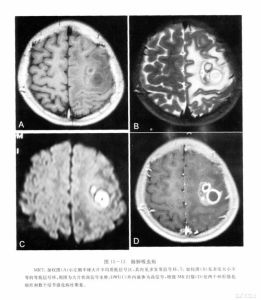

4.顱骨片有囊壁鈣化影。頭顱CT掃描和磁共振檢查可見囊腫。

3.頭顱CT掃描和磁共振檢查可見囊腫顱骨片有囊壁鈣化影如合併胸肺型X線檢查可見肺部有明顯改變

②肉芽腫或囊腫期,穴窟病變周圍出現炎症反應,組織壞死液化,其內含夏科一 雷登結晶,周圍為肉芽組織及纖維囊壁形成囊腫、肉芽組織,內有大量蟲卵並可找到成蟲。蟲體有遊走的習性,常從囊 腫內遊走到周圍腦組織,形成新囊腫。諸囊腫間有遂道相通,形成多房性囊腫;

3.腦瘤型除頭痛,噁心,嘔吐等一般顱內壓增高症狀外,尚可有肢體運動障礙及顱 神經損害等定位體徵,可出現視乳頭水腫。腦脊液壓力增高,白細胞及蛋白可輕度增高。此型約相當於蟲體腦內時間較 長,形成較大的多房性囊腫肉芽腫。